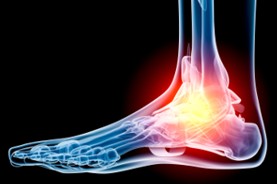

Shockwave Therapy

We offer the new, advanced technology known as Extracorporeal Radial Shock Wave Therapy (ESWT) or (RSWT). This technology reduces or eliminates many types of chronic pain. Radial Shockwave Therapy is fast, safe, non-invasive and very effective in treating many problems for which, traditionally, patients were unable to receive effective medical treatment.